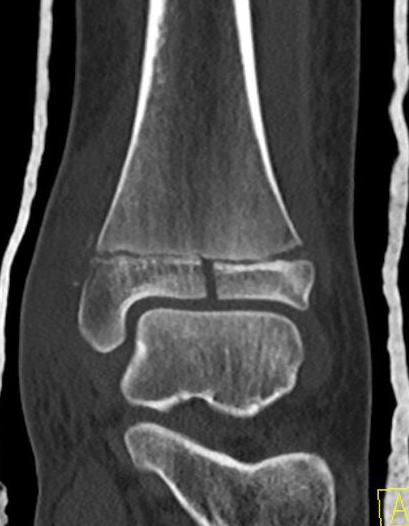

Triplanar Fracture

Definition

Fracture in coronal, sagittal and transverse planes

- crosses epiphysis

- passes through growth plate

- extends into metaphysis

Xray

AP xray: Salter-Harris type III / Tillaux

Lateral xray: Salter-Harris Type II

CT

Coronal images: Salter-Harris type III

Sagittal images: Salter-Harris type II

Axial images: 3 point star